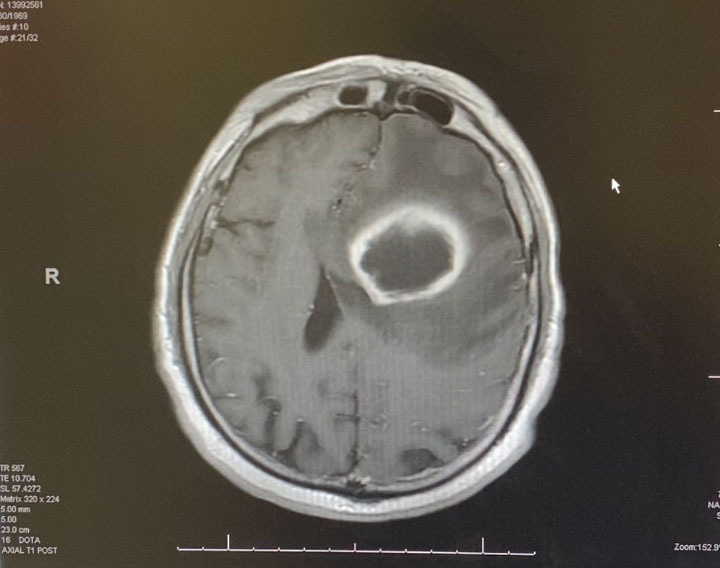

Image 1: Pre-treatment axial post contrast MRI.

This is a 50 year old man who last year had undergone gastrectomy for gastric cancer. He presented now with new onset of lethargy and aphasia, with both a receptive and expressive component . He was also experiencing intermittent bradycardia. Brain imaging showed a 3 cm ring enhancing , fluid filled mass in the left frontal region with significant surrounding edema, mass effect, and midline shift. (Image 1 shows axial post contrast MRI. ) Recent imaging of the body had shown no evidence of active metastatic disease.